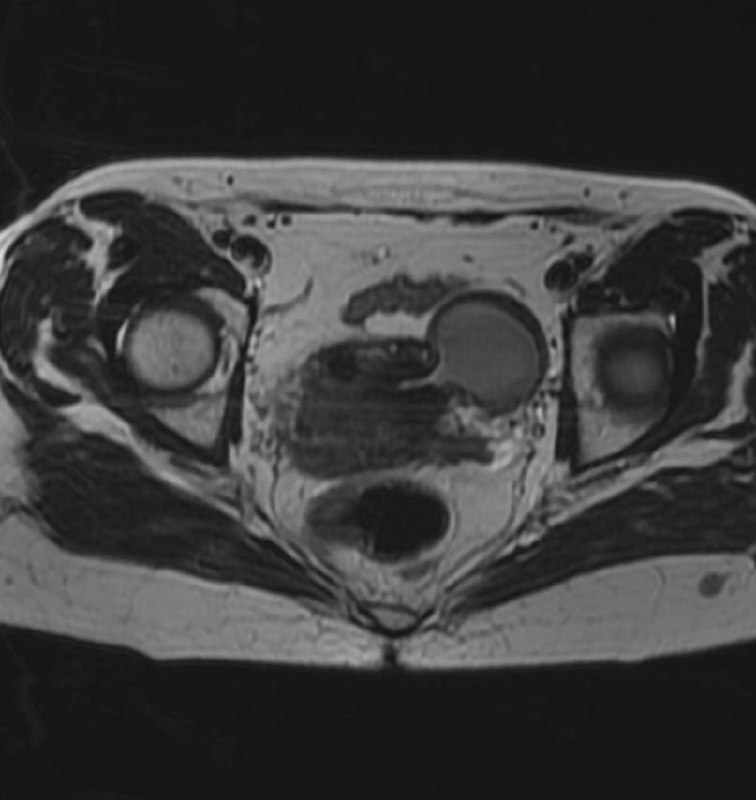

Дивертикул матки у женщины 45 лет.

Дивертикул матки - это редкий врожденный порок развития, вызванный аномальным слиянием мюллеровых протоков.

Диагноз дивертикула матки затруднен, и его часто неправильно диагностируют как другую аномалию Мюллерова протока (например, кровь в рудиментарном роге матки), миому матки с дегенерацией, эндометриому или геморрагическую кисту яичника.

Встречается так редко, что я, вот, первый раз сам увидел, и то, спасибо коллеге из Алма-Аты.

Спасибо, Диас!